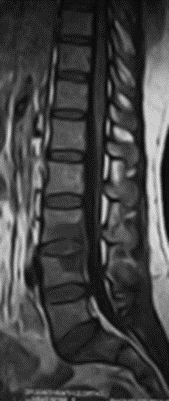

At presentation she had severe paraspinal spasm with movement restriction and no neurological deficits. Radiographs revealed a minimal reduction in L4/5 disc space . Hematological evaluation elevated showed TLC, ESR, CRP. MRI showed evidence of discitis at L4/5 with adjacent vertebral reactive changes( FIG 1,2). With a working diagnosis of post partum spondylodisctis she underwent a septic screening ( sputum, urine, blood cultures) and a CT guided biopsy which turned out to be negative. Considering her significant back pain  with limitations in suggesting antibiotics  she was suggested surgical debridement and fusion at L4/5. She underwent PLIF L4/5 under GA and had a drastic early pain relief . She was mobilized on post operative day – 1 with lumbo sacral brace. Her pain reduced significantly ( VAS 2/10) which needed minimal analgesics ( once a day paracetamol 1 gm intravenous infusion )for 5 days . She was able to turn in bed and sit to nurse the child. Her intraoperative tissues sent for culture grew pseudomonas which was sensitive to cefaperazone + sulbactum. She was initiated on intravenous antibiotics for 2 weeks duration and was followed up with further 4 weeks of oral antibiotics . Radiographs revealed fusion at L4/5 at 3 months( FIG 3,4) of follow up with serological markers normalizing by 6 weeks.

Fig 1: T2 MRI – L4/5 spondylodiscitis

Fig 2: T1 MRI – L4/5 spondylodiscitis